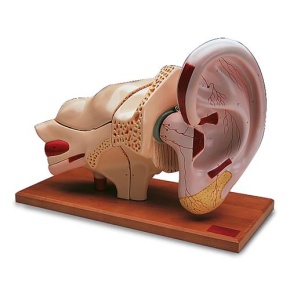

Riesen-Ohr, 5-fache Größe, 3-teilig

Modell, Riesen-Ohr, 5-fache Größe, 3-teilig